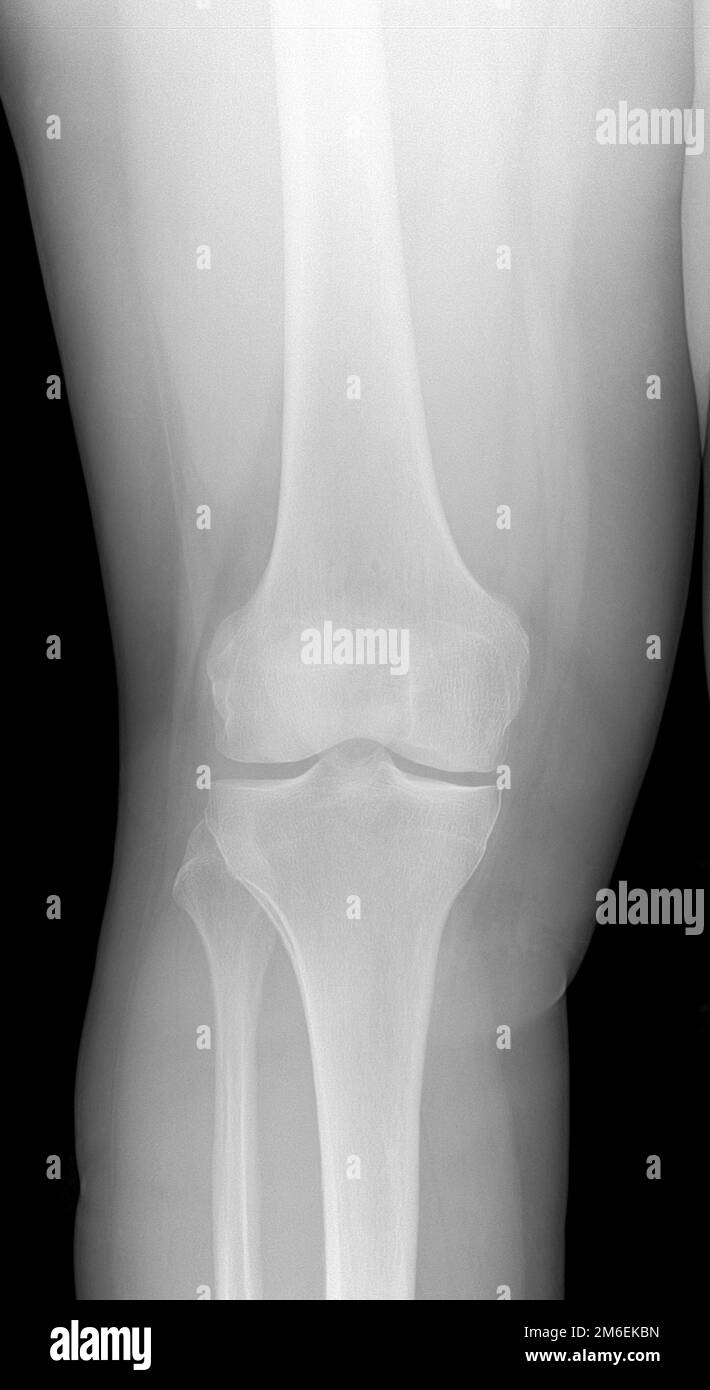

Knee Arthritis, MRI Stock Image C027/1212 Science Photo Library

What Is Radiographic Knee Osteoarthritis . The diagnosis of osteoarthritis is based primarily on the history and physical examination, but radiographic findings, including asymmetric joint space narrowing, subchondral sclerosis,. Radiographs and mri scans are commonly used imaging techniques in the assessment of knee osteoarthritis. Knee osteoarthritis (oa) is one of the most common and debilitating degenerative joint diseases worldwide. Conventional radiography remains the most widely available imaging modality in clinical practice in knee osteoarthritis. The purposes of this systematic review were to (1) identify the commonly used definitions of radiographic koa progression, (2). Objectives the aim was to study the development of radiographic knee osteoarthritis (rkoa) in individuals with knee pain over 2. Our objectives were to identify estimates of the prevalence of radiographic knee oa in adults with knee pain and of knee pain in.

The diagnosis of osteoarthritis is based primarily on the history and physical examination, but radiographic findings, including asymmetric joint space narrowing, subchondral sclerosis,. Knee osteoarthritis (oa) is one of the most common and debilitating degenerative joint diseases worldwide. Objectives the aim was to study the development of radiographic knee osteoarthritis (rkoa) in individuals with knee pain over 2. Conventional radiography remains the most widely available imaging modality in clinical practice in knee osteoarthritis. Radiographs and mri scans are commonly used imaging techniques in the assessment of knee osteoarthritis. Our objectives were to identify estimates of the prevalence of radiographic knee oa in adults with knee pain and of knee pain in. The purposes of this systematic review were to (1) identify the commonly used definitions of radiographic koa progression, (2).